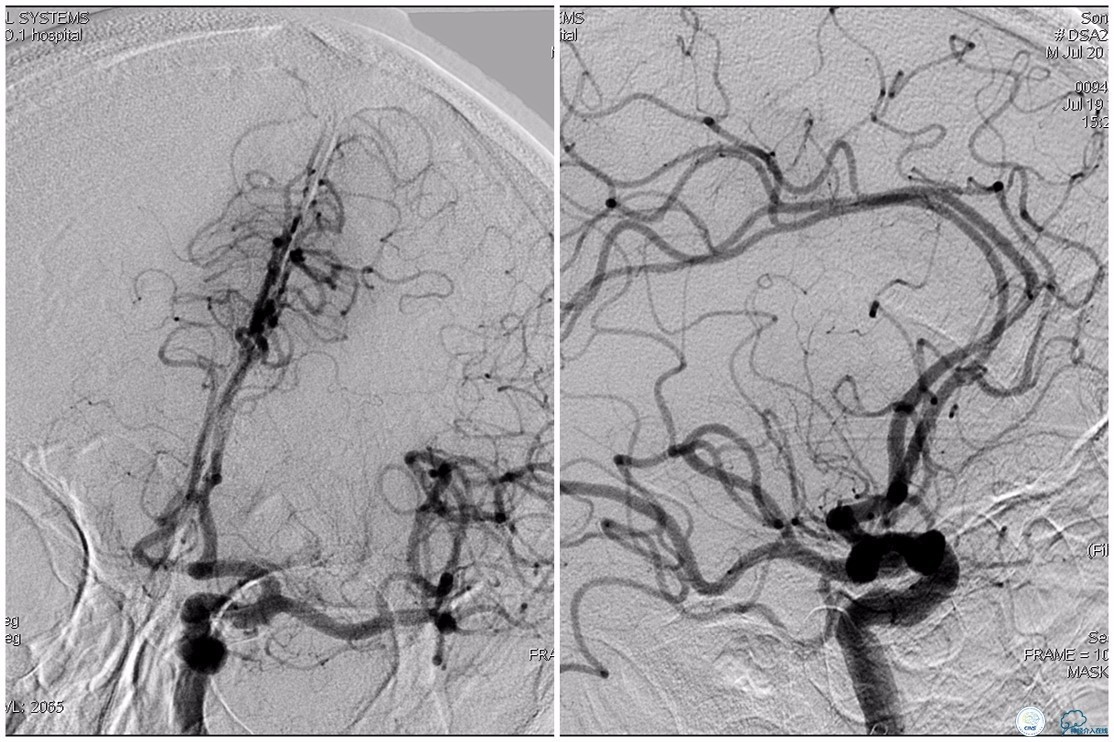

双侧大脑前动脉完全显影,TICI 3级,TOR 261min。

术后头颅CT复查。

术后复查头颅CTA。

术后复查头颅MRI。

术后第二天患者意识清,言语清,右上肢肌力1级,右下肢肌力3级,左上肢肌力5级,左下肢3级。

术后90天随访右上肢肌力3级,左上肢肌力5级,双下肢肌力4级,mRS评分3分。